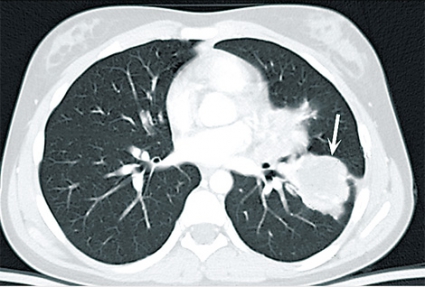

Fall 1. En 11-årig svenskfödd flicka insjuknade våren 2004 med intermittent hosta och blodtillblandat expektorat. Under sommaren utfördes en datortomografi (DT) av lungorna i Turkiet. Antibiotika gavs och föräldrarna informerades om att hon hade ekinokockos. DT på Karolinska universitetssjukhuset i Huddinge visade en oval cystisk struktur, 3,5 cm i diameter, i vänster lungas lingula. En liknande struktur påvisades i vänster underlob. I levern fanns en 5 cm stor cysta (Figur 1). Serologi var positiv avseende ekinokockos. Flickan vistades vartannat år en längre tid hos sin farfar i en by i centrala Turkiet. Detta är ett område med högendemisk förekomst av Echinococcus granulosus. Farfar är fårfarmare som slaktar hemma och ger sina hundar slaktavfall. I november 2004 fick flickan albendazol (Zentel) motsvarande 14 mg/kg/dag uppdelat på två doser. Ny DT efter fyra månader visade att cystorna i lungan minskat kraftigt i storlek. Efter ett års behandling hade de nästan helt försvunnit. Albendazol gavs i 18 månader. Ultraljud fyra år senare visade att cystan i levern minskat till 2,7 cm, och den bedömdes som inaktiv (CE4).

Hos människa orsakar E granulososus-infektion långsamt växande, icke invasiva cystor. Den vanligaste lokalisationen är levern (60–80 procent), följt av lunga (15–20 procent), mjälte (5 procent), skelett/muskulatur (4 procent) och övriga organ (2–5 procent) [1-3]. De som har cystor i lungan har ofta även cystor i levern. Vanligast är dock en enda solitär cysta i levern. Cystorna växer 1–10 (50) mm/år, och det finns en stor tendens till spontanläkning som ökar med tiden. Levercystor verkar växa långsammare än lungcystor [1]. Aktiva cystor innehåller vanligen dottercystor (Figur 4) och ett stort antal några tiondelar av en millimeter stora protoscolices. När cystan degenererar försvinner dottercystorna, innehållet blir homogent och väggen förkalkas. Ekinokockcystor i lungan kan inte förkalkas. Cystornas aktivitet kan klassificeras enligt ett modifierat WHO-schema baserat på ultraljudsundersökning [2, 3]. De orsakar en inflammatorisk reaktion i den omgivande vävnaden, vilket leder till bildning av en fibrotisk kapsel av varierande tjocklek utanför själva cystmembranet och ibland till uppkomst av fistlar till omgivande strukturer, framför allt gallgångar.